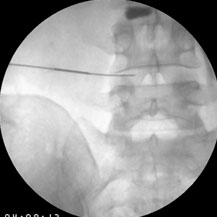

Ozone neucleolysis or ozone discectomy is a non-operative intervention for slipped disc / disc prolapse & discogenic pain. Ozone discectomy is a day care procedure and general anaesthesia is not required. Total cost of the procedure is much less and is very safe compared to other procedures. It has been implicated as one of the important cause of low back pain radiating to limbs. Apart from conservative therapy all other forms of treatment aim at decompressing the nerve roots. These can be done by taking the disc out by surgery or by decompressing the foremen and disc by different interventions. The various treatment options have confused clinicians due to significant failure rate associated with different kinds of surgeries as well as with different interventions.

Epidural steroid injection, transformational epidural decompressions has a high success rate (up to 85%) but chances of recurrences are there specially if these interventions are done at later stage. Chemonucleolysis using chymopa pain has also high success rate (80%) with low recurrences but not popular owing to the chances of anaphylaxis following intradiscal chymopa pain injection. Injection of ozone for discogenic radiculopathy (low back pain with radiation to legs) has developed as an alternative to chemonucleolysis and disc surgery owing to its high success rate, less invasiveness, fewer chances of recurrences and remarkably fewer side effects.

The action of ozone is due to the active oxygen atom liberated from breaking down of ozone molecule. When ozone is injected into the disc the active oxygen atom called the singlet oxygen or the free radicle attaches with the proteo-glycan bridges in the jelly-like material or nucleus pulposus. They are broken down and they no longer capable of holding water. As a result disc shrinks and mummified and there is decompression of nerve roots. It is almost equivalent to surgical discectomy and so the procedure is called ozone discectomy or ozonucleolysis. Besides, it has an anti-inflammatory action due to inhibitions of formation of inflammation producing substances and tissue oxygenation is increased due to increased 2,3 diphosphoglycerate level in the red blood cells. All these leads to decompression of nerve roots, decreased inflammation of nerve roots, increased oxygenation to the diseased tissue for repair work.

Ozone nucleolysis or ozone discectomy has a success rate of about 80%. On the other hand surgical discectomy has much higher side effects compared to remarkably few side effects of ozone discectomy. Ozone discectomy is usually a day care procedure and general anaesthesia is not usually required. Total cost of the procedure is much less than that of surgical discectomy. All these facts have made this procedure very popular at European countries. It is also gaining popularity in our country due to low cost, less hospital stay, no post-operative discomfort and morbidity and very few side effects.